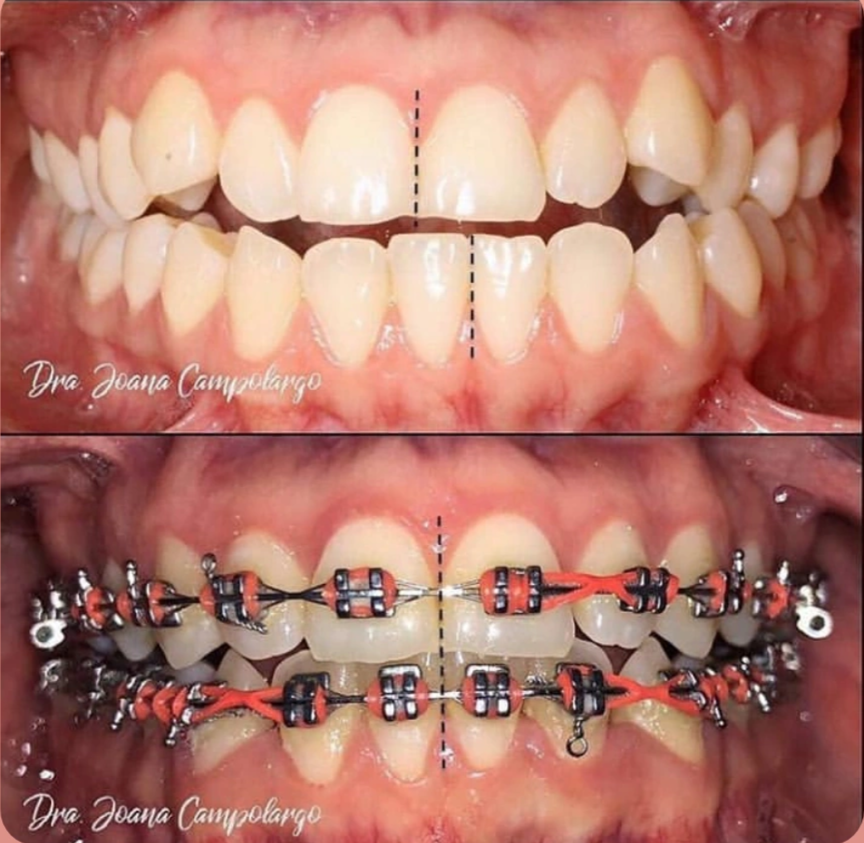

Orthodontics

Orthodontics focuses on correcting misaligned teeth and jaws, often using braces or clear aligners. This treatment improves not only the appearance of the smile but also bite function and overall dental health.

• Treatments: Traditional Metal Braces, Ceramic Braces, Invisible Aligners (Clear Path/Invisalign).

• Benefit: A straight, healthy, and perfectly aligned smile.

Dental Braces Treatment